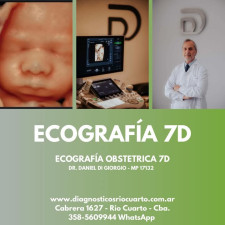

Diagnósticos Río Cuarto tiene una amplia trayectoria brindando atención médica en diagnóstico por imágenes en la región. Se ha consolidado como un centro con equipamiento tecnológico avanzado, ofreciendo servicios para el diagnóstico temprano y la prevención de enfermedades. La institución se ha comprometido con la calidad y la seguridad, asegurando una atención integral a sus pacientes.

- Ecografías 7D (Obstétricas, generales)